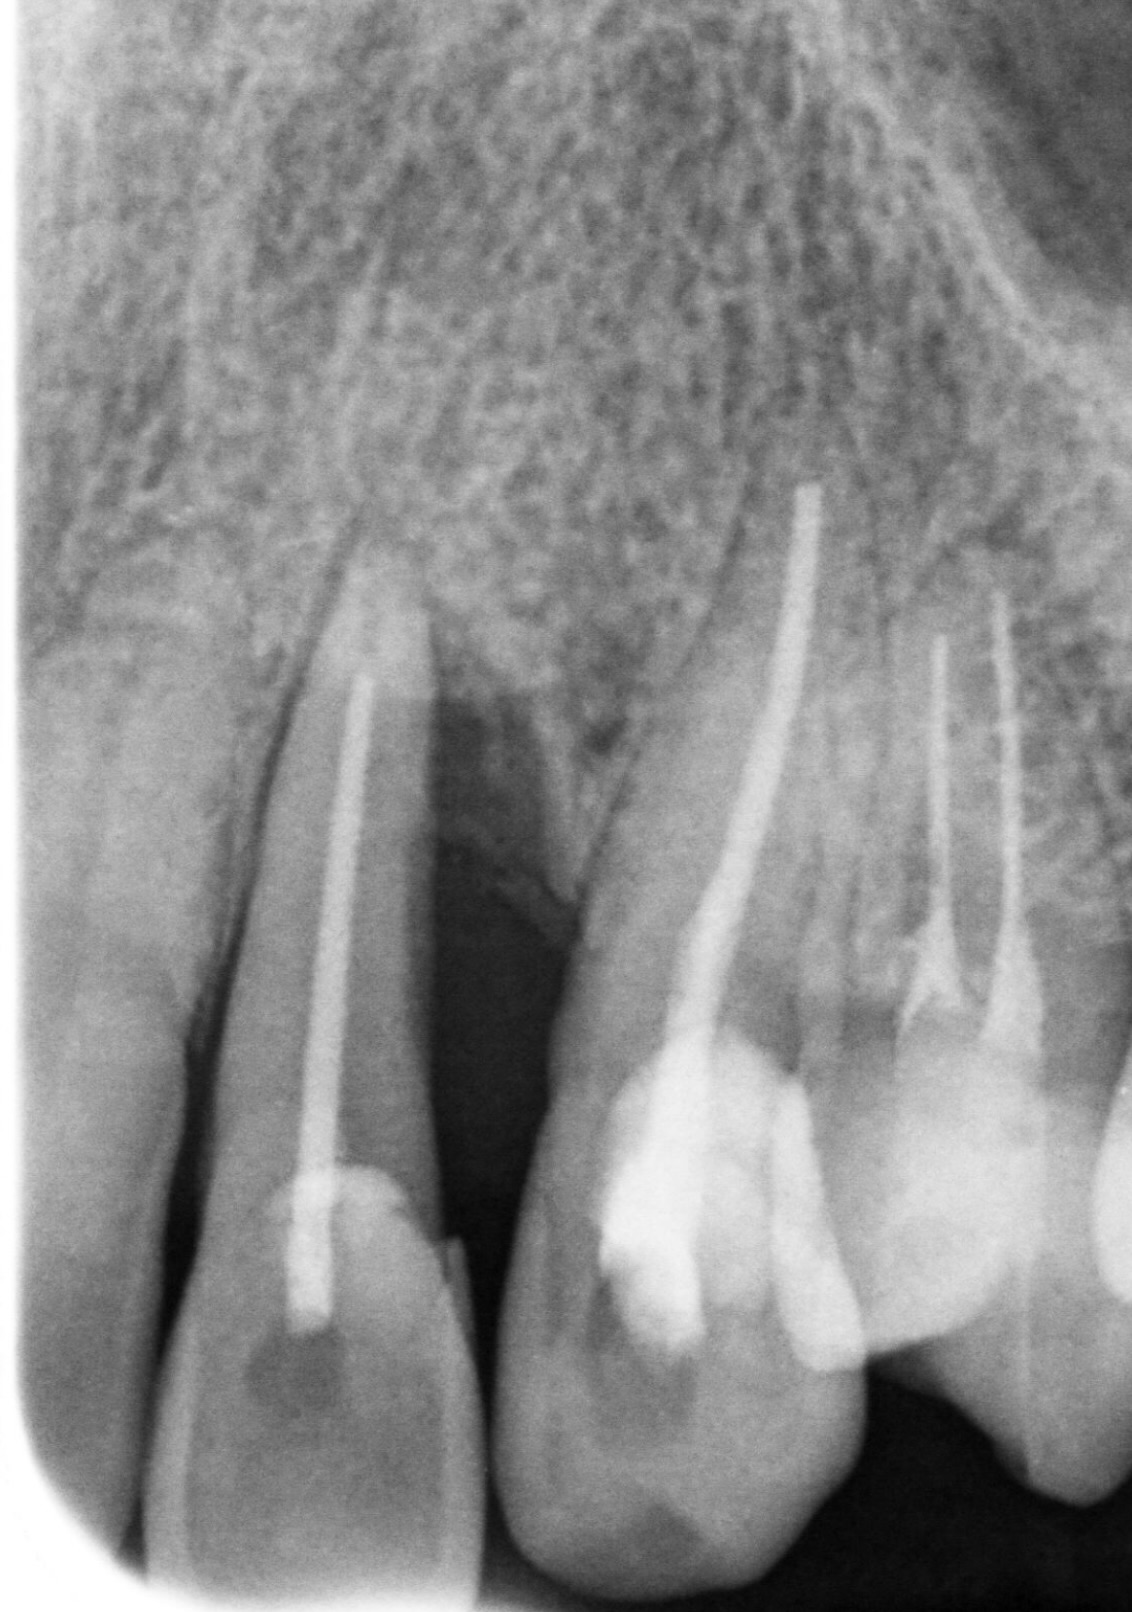

レントゲンを撮ると根の先の方まで歯周病で骨が溶けていました。(赤線部)

そして術後半年ほどでレントゲン上で、完全では無いですが

歯周病で溶けてしまった骨が回復してきたのが確認できました。

治療前